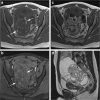

Objectives: The use of magnetic resonance (MR) imaging in differentiation between benign and malignant adnexal masses in children and adolescents might be of great value in the diagnostic workup of sonographically indeterminate masses, since preserving fertility is of particular importance in this population. This systematic review evaluates the diagnostic value of MR imaging in children with an ovarian mass.

Results: Sixteen paediatric and 18 adult studies were included. In the included studies, MR imaging has shown good diagnostic performance in differentiating between benign and malignant ovarian masses. MR imaging techniques including diffusion-weighted imaging (DWI) and dynamic contrast-enhanced (DCE) imaging seem to further improve the diagnostic performance.

Conclusion: The addition of DWI with apparent diffusion coefficient (ADC) values measured in enhancing components of solid lesions and DCE imaging may further increase the good diagnostic performance of MR imaging in the pre-operative differentiation between benign and malignant ovarian masses by increasing specificity. Prospective age-specific studies are needed to confirm the high diagnostic performance of MR imaging in children and adolescents with a sonographically indeterminate ovarian mass.

Key points: • MR imaging, based on several morphological features, is of good diagnostic performance in differentiating between benign and malignant ovarian masses. Sensitivity and specificity varied between 84.8 to 100% and 20.0 to 98.4%, respectively. • MR imaging techniques like diffusion-weighted imaging (DWI) and dynamic contrast-enhanced (DCE) imaging seem to improve the diagnostic performance. • Specific studies in children and adolescents with ovarian masses are required to confirm the suggested increased diagnostic performance of DWI and DCE in this population.